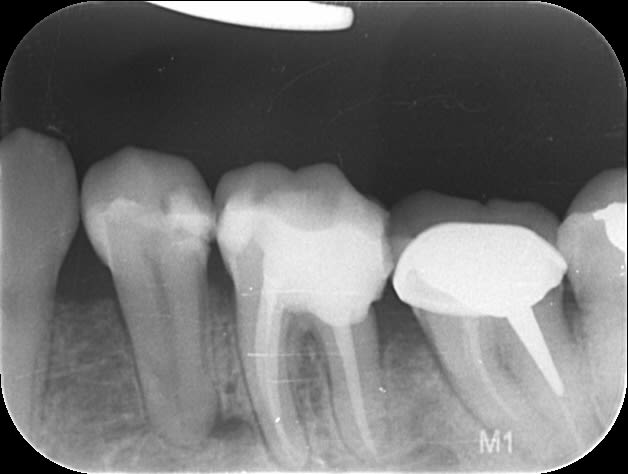

Photo 1:radio finale endo faite en juillet, difficile pour l'anesthésie j'ai dû en rajouter 1 carpule en intralig.

Photo 2 : Bref je revois la patiente fin Aout à mon retour et elle me dit qu'elle à toujours mal même si ça va mieux 2 : gencive bien gonflée entre 36 et 35, 35 douloureuse mais vitale.

Et aujourd'hui, elle est contente plus aucune douleur sauf que en bouche je vois un bout d'os entre 35 et 36 et à la radio ... (image 3)

Icxtvlul0dyh3ebpv5kp - Eugenol

Vbtdxmzapfzz8zc4a75z - Eugenol

Ys9pusork0tralysz0zk - Eugenol